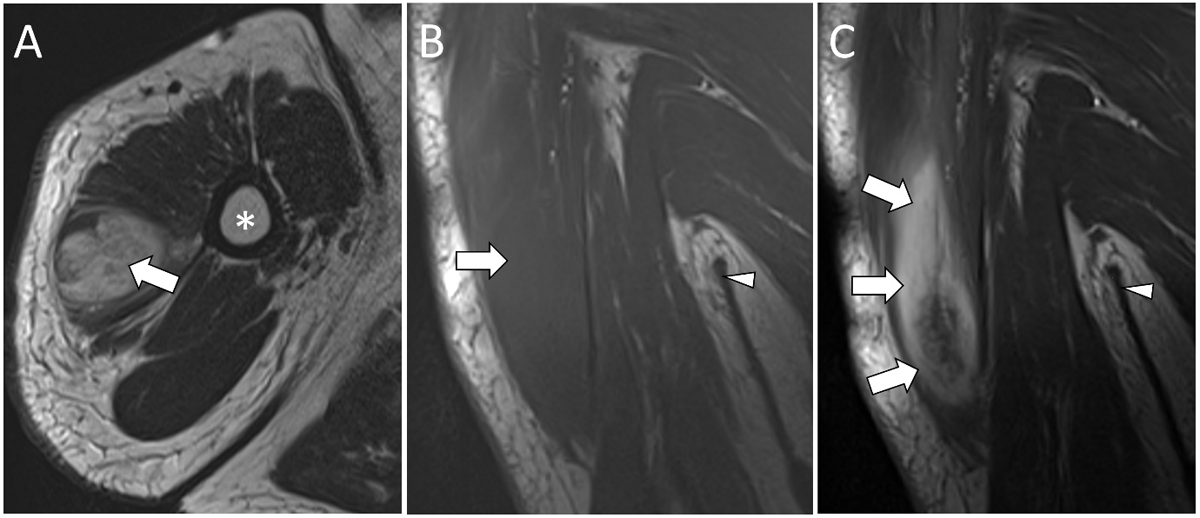

Figure 4

MRI images of PM in the right deltoid muscle demonstrate a hyperintense lesion (white arrow) on axial T2WI (A) and an isointense lesion on coronal T1WI (B) with a marked enhancement on coronal post-contrast T1WI (C) (white arrows). Humerus (*). Axilla (white arrowhead).